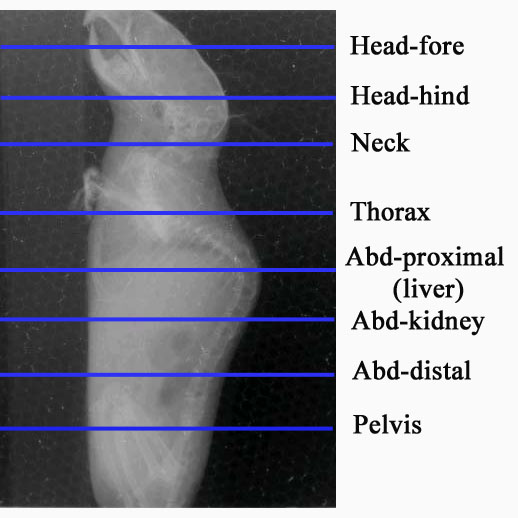

| Level I - Micro-CAT Data for MEM766N1-F-200 | |||||||

| 200 | MEM766N1-F-200 | 2004-11-04 | 2005-04-01 | F | het | 138864 | |

| No abnormalities were seen in gross skeleton, thorax, and abdomen. Liver, kidney, and spleen appeared normal in size, shape and position. The rate of excretion of contrast media by the kidneys was within normal limits, reflecting normal function. |